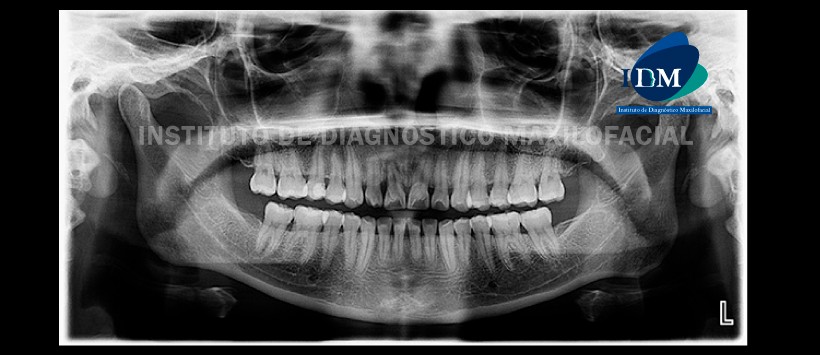

Paciente femenino, 27 años de edad, es referido al Instituto de Diagnóstico Maxilofacial (IDM) para evaluación tomográfica de pieza 1.1.

En la radiografía panorámica (Figura 1) se observa proceso osteolítico eri-radicular en pieza 1.1, ausencia de terceras molares.

A la evaluación de la tomografía volumétrica (CBCT) cortes axiales (Figura 2), transaxiales (Figura 3) y tangenciales (Figura 4), se aprecia a la pieza 1.1 con alteración en la anatomía y morfología dentaria caracterizada por la bifurcación radicular (raíz vestibular y palatina) y por la presencia de surco corona radicular en superficie mesial y distal siendo la distal la mas acentuada. Además la pieza se asocia a proceso osteolítico peri-radicular que ocasiona la pérdida de la tabla ósea vestibular y aumento de la densidad ósea circundante (osteítis condensante).

Como hallazgo tomográfico se encontró la presencia de dens invaginatus en pieza 1.2

En las reconstrucciones 3D se observan con detalle la bifurcación radicular de la pieza 1.1 así como la presencia de los surcos proximales (Figura 5 y 6).

– Pieza 1.1 bifurcación radicular con surco palato-radicular en superficies proximales, asociado a proceso osteolítico peri-radicular.